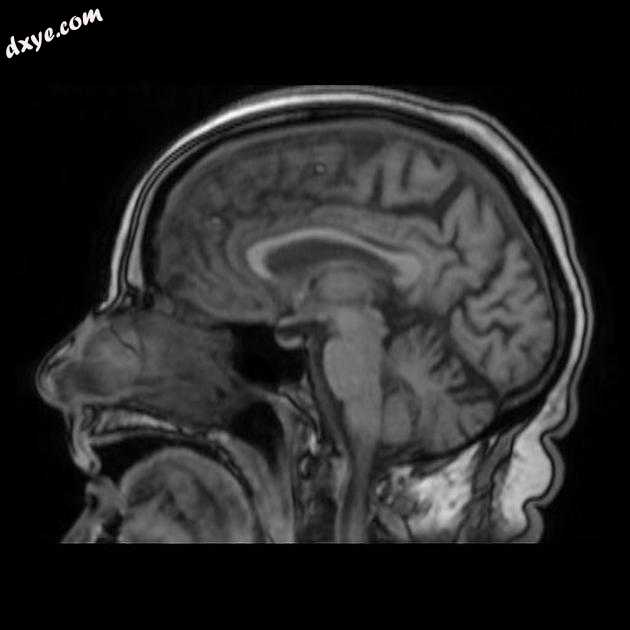

Sagittal T1

MRI 序列显示左侧大脑中动脉 (MCA) 区域分布中的弥散受限区域,在 FLAIR 序列上不可见。在 GE 序列上没有看到出血性转化。 MRA 3D-TOF 显示左侧大脑中动脉完全闭塞。

早期超急性大脑中动脉 (MCA) 区域梗死的 MRI 特征。